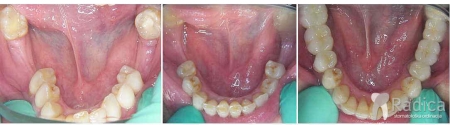

U sljedećem primjeru je fiksna ortodontska terapija rađena samo u donjoj čeljusti. Nakon toga pacijent je upućen svom stomatologu koji je napravio nove protetske radove u gornjoj i donjoj čeljusti.